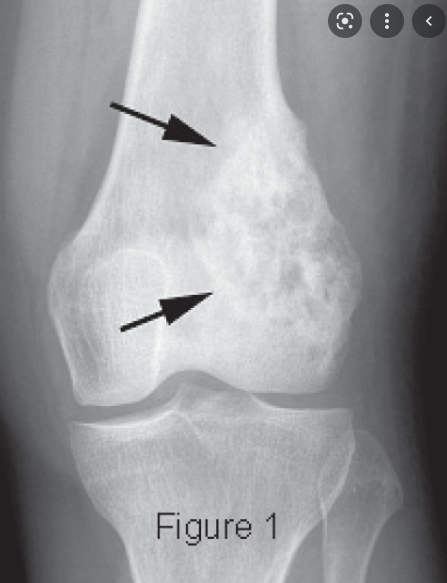

How can you spot osteosarcoma on an X-ray?

A

1. ill-defined lesion with an indistinct zone of transition

2. sclerotic or lytic areas within the lesion

3. cortical destruction

4. codman triangle

5. sunray spicules

What is codman triangle?

the triangular area of new subperiosteal bone that is created when a lesion raises the periosteum away from the bone.

Where do osteosarcomas most commonly arise?

• around the knee

• proximal humerus

• femur